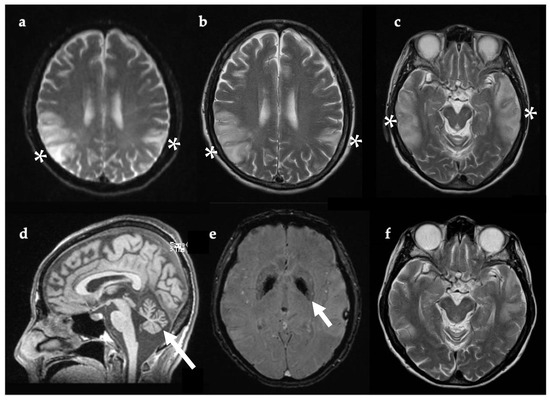

Following clinical deterioration, she was transferred to NHNN. Brain MRI (three weeks after symptom onset, Figure 1) showed multi-focal areas of recent parenchymal insult, characterised by cortical and subcortical white matter signal abnormalities and mild parenchymal swelling, affecting different vascular territories. The EEG had a slow background with no seizure activity, but occasional left temporal sharp waves.

Figure 1. Coronal T2-FLAIR MRI, 21 days after symptom onset. There are multiple areas of supra-tentorial encephalomalacia bilaterally within the temporo-parieto-occipital lobes with parenchymal T2 signal change, thinning of gyri, and white matter volume loss ((a,b), white arrows). Multiple vascular territories are involved. Abbreviations: FLAIR, fluid attenuated inversion recovery imaging.